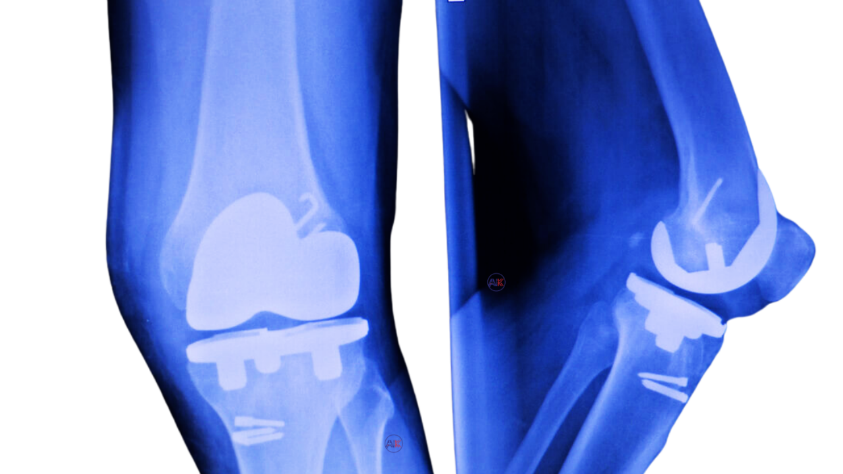

COMPLICATIONS OR FAILURE OF A PREVIOUS KNEE REPLACEMENT

This condition occurs when a previously implanted knee replacement begins to fail, resulting in discomfort, instability, and potential joint problems.